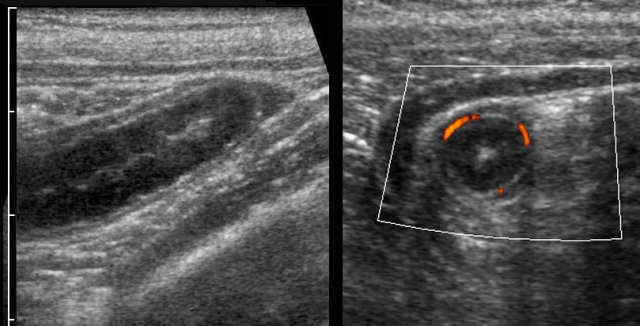

In these two patients initially the mucosal thickening of the terminal ileum as a sole US finding was interpreted as Crohn’s ileitis or infectious ileitis.

A second US exam revealed the underlying appendicitis (arrow) causing secondary thickening of the neighboring ileum.